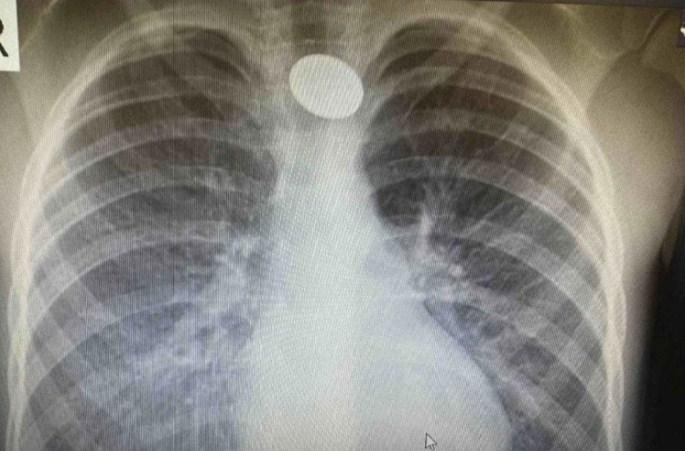

U Bolnicu “Srbija” u Istočnom Sarajevu u roku od dva sata primljena su dva dječaka uzrasta od 16 mjeseci i pet godina koja su progutala novčiće, saopšteno je danas iz ove zdravstvene ustanove.

On je naveo da je šesnaestomjesečnom dječaku sinoć hirurškim putem iz jednjaka uklonjen novčić od 10 feninga.

“Nakon urađene anamneze, dobijen je podatak da je dječak u igri sa stola uzeo kovanicu od 10 feninga i progutao, nakon čega je povraćao u više navrata. Na svu sreću nije dolazilo do gušenja, niti je gubio svijest i imao problem sa disanjem”, rekao je Pejić.

On je napomenuo da su se roditelji na vrijeme javili u najbližu ustanovu, gdje je utvrđeno da je riječ o stranom tijelu u jednjaku.

Prema Pejićevim riječima, nedugo nakon ove situacije, u urgentni blok bolnice stiglo je petogodišnje dijete sa sumnjom da ima strano tijelo u jednjaku.

Roditelji su rekli da je dječak odmah nakon večere progutao kovanicu i da nema nikakve tegobe.

Nakon dijagnostičke obrade, i ovom dječaku je iz jednjaka uklonjena kovanicu od 10 feninga.